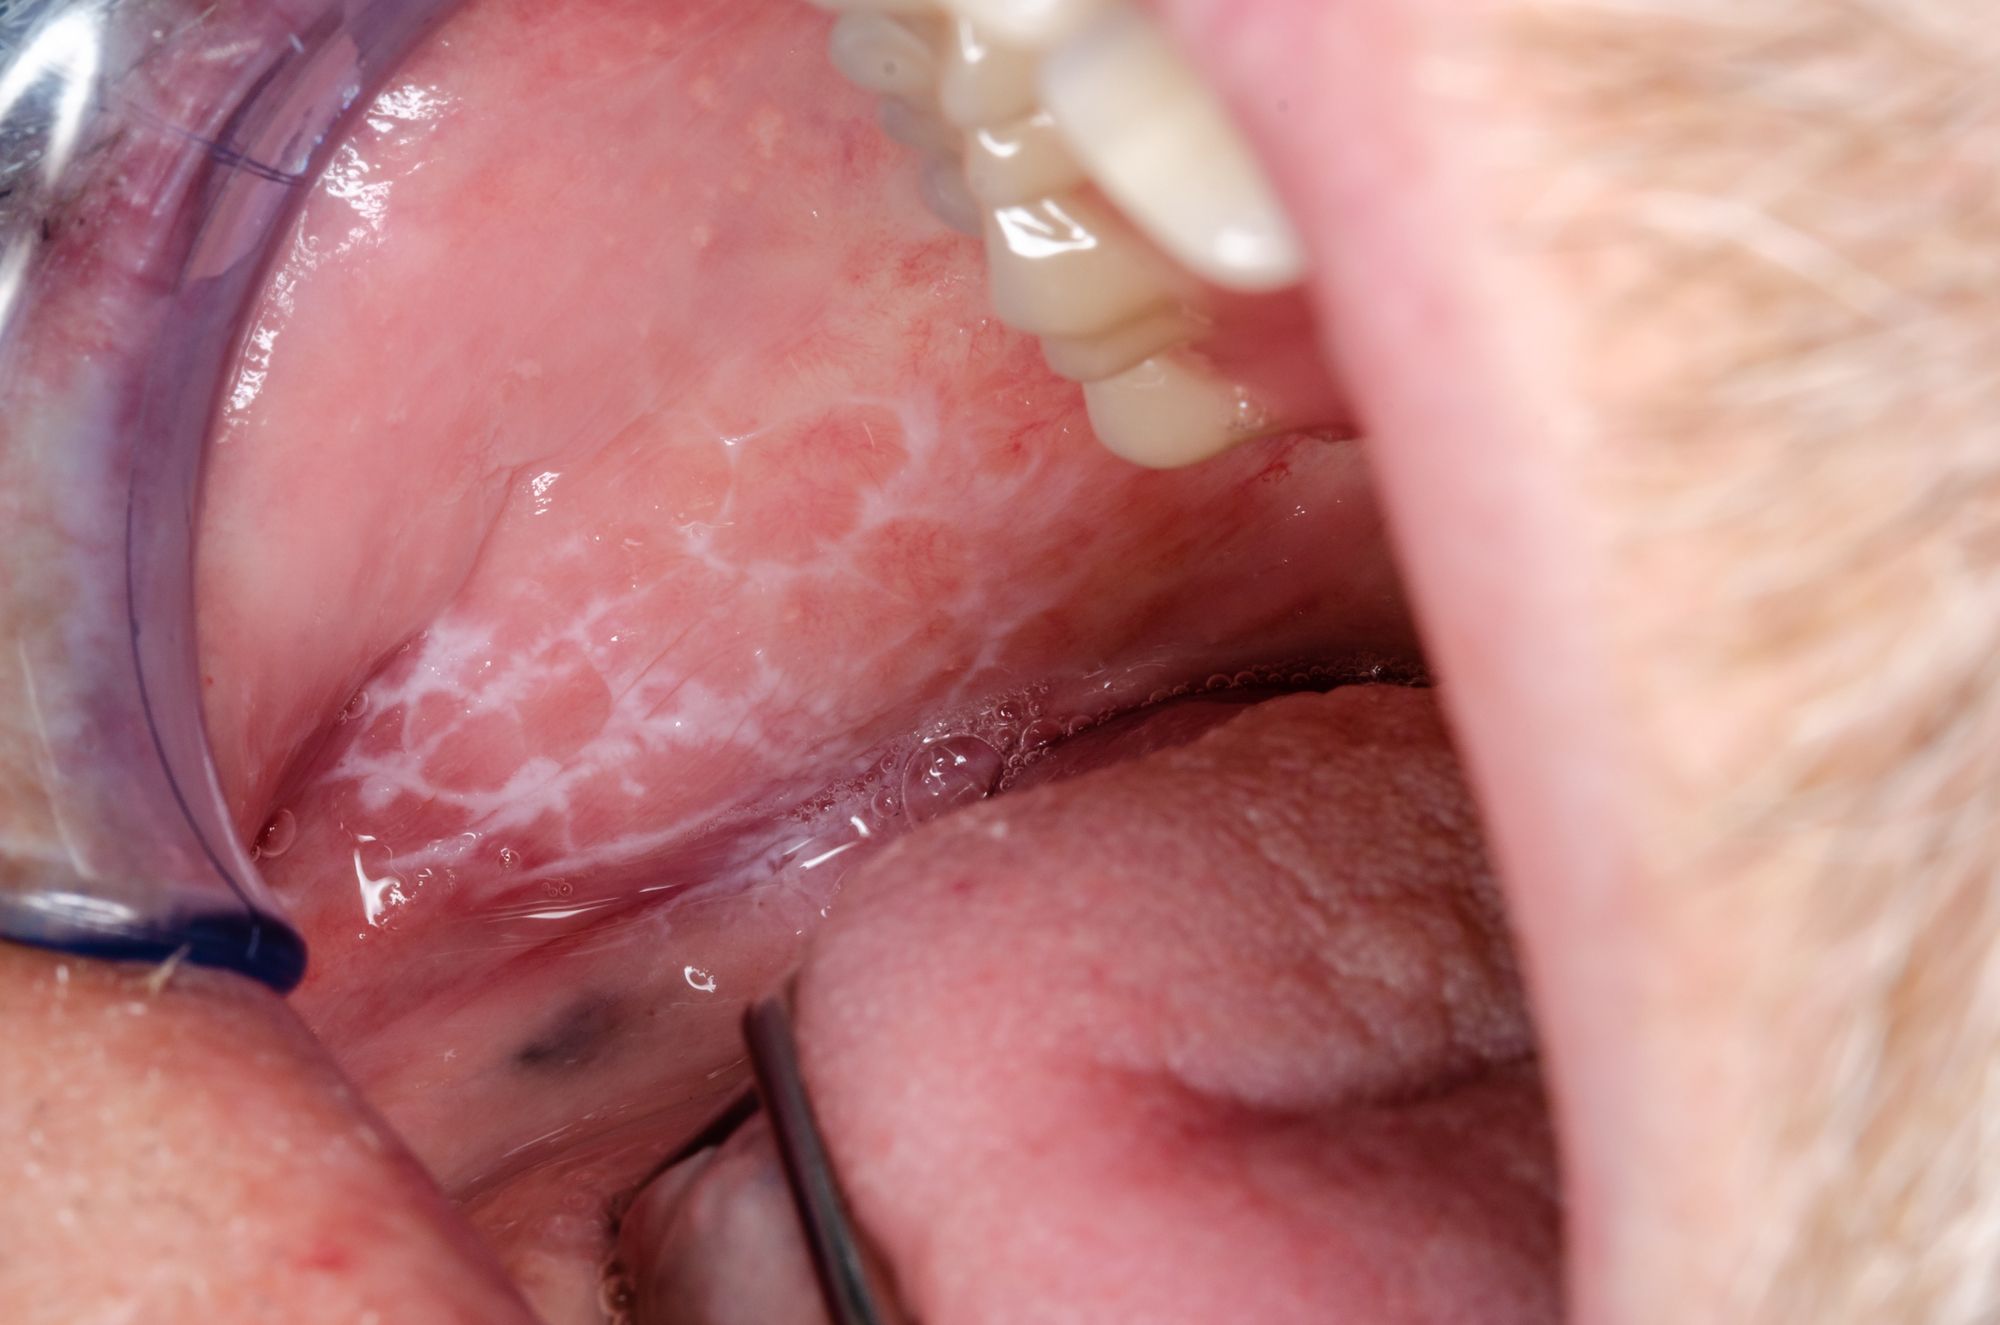

Oral Lichen Planus and Malignant Transformation. Photo courtesy of Dirk/stock.adobe.com.

The typical OLP we see in patients’ mouths appears in a reticular pattern and is commonly seen on the cheeks as lacy web-like white threads that are slightly raised. These threads are sometimes referred to as Wickham’s Striae. The erosive (atrophic) pattern of OLP can affect any mucosal surface like the cheeks, tongue, and gingiva. It appears as bright red due to the loss of the top layer of the mucosa in the area affected. Individuals with erosive OLP often report discomfort when eating and drinking, especially with extremes of temperature, acidic, coarse, or spicy foods.1

Severe cases of OLP can become ulcerated which may be very painful, even without eating or drinking. There’s 1 other type of lichen planus which is plaque-like and gives the appearance of a dense thickening or the mucosal tissue.1